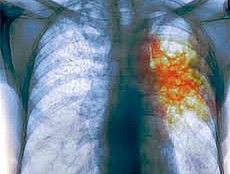

Днепропетровская область входит в список самых проблемных областей по заболеваемости туберкулеза. А в целом по Украине на 100 тыс. населения 67 больных туберкулезом.